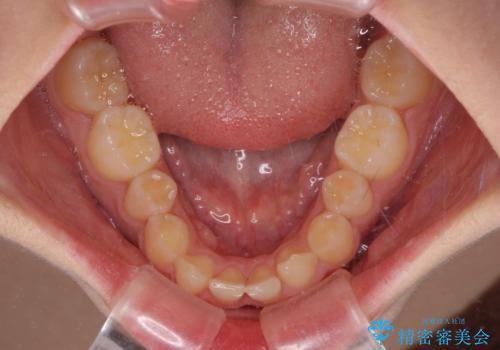

- 下顎前歯が欠損しており、前歯がデコボコとなっている歯並びを気にして来院された患者様です。

下顎の左右側切歯2本が欠損しており、上顎歯列がデコボコとなっている状態でした。

下顎歯列に対して上顎歯列が相対的に大きくなっているため、デコボコとなっているだけでなく、下顎前歯が見えなくなるくらいのディープバイトにもなっていました。